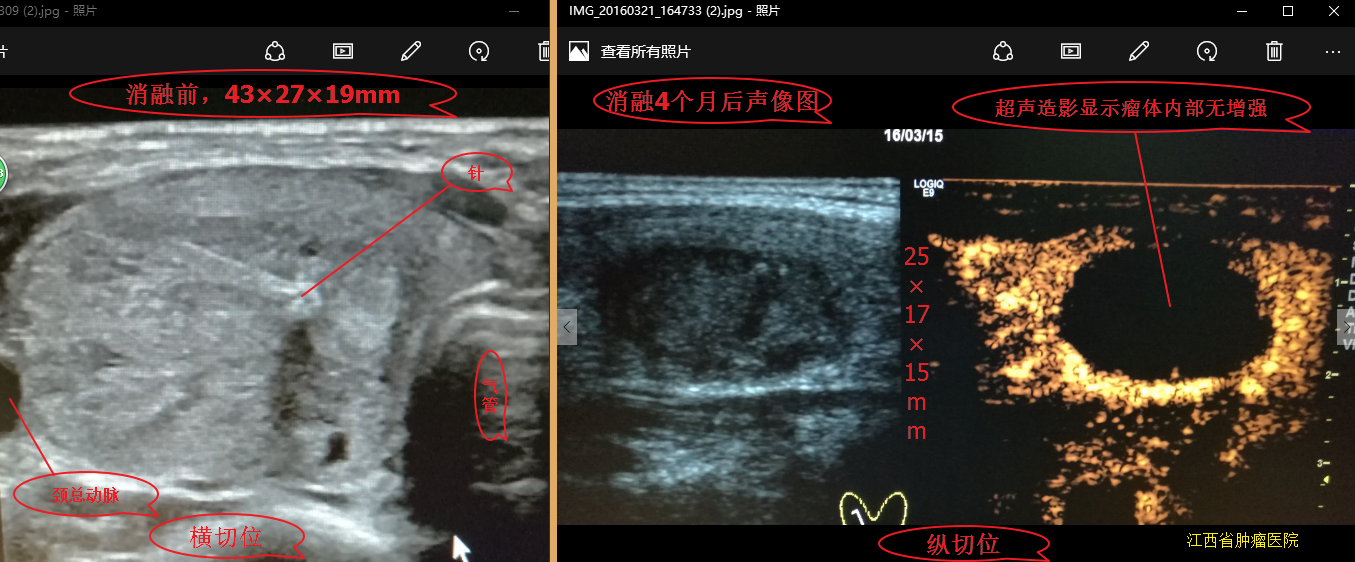

甲状腺结节微波消融术后,随访效果图!